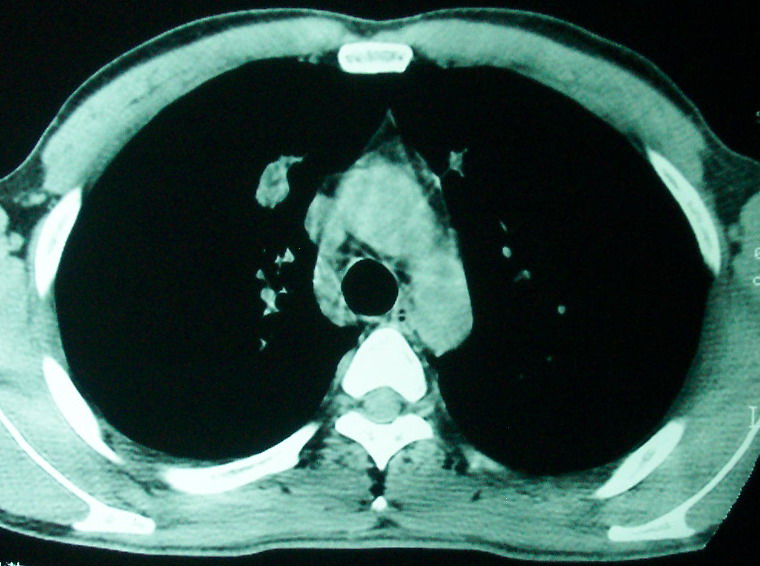

m      37y      发热   咳脓痰月余      ct肺脓肿但住院抗炎治疗后双肺内结节不知该如何解释

治疗后见左肺下野病灶较前缩小但双肺内结节影似无变化请较各位老师该如何下结论    治疗前wbc14.5 治疗后wbc 11.0

血源性肺脓肿,一般由原发感染灶引起脓毒败血症,在肺部形成小脓肿,病变变化快,容易形成肺气囊,脓气胸,主要与转移瘤鉴别,通过临床病史可分

结合病史考虑血源性肺脓肿,与转移瘤鉴别

结合临床发热,咳痰考虑为血源性肺脓肿,不过双肺结节又在肺的边缘,还是小心一点,抗炎后复查吧

除了肺内多发结节和左肺下叶的浓疡病灶,还应注意满肺散在的小结节影,还有右上肺前段支气管内膜不光整这些细节,结合病史,肺内多发结节应考虑结核性肉芽!

如果你仔细的同层面对比,你会发现所有的病灶均有比较明显的吸收、缩小。病变的形态,特别是脓肿的形态、壁的厚薄、内壁均有很大的变化,均在往好的方面发展。与临床症状、血像均符合,治疗效果比较显著,就是肺脓肿并双肺的化脓性炎症灶。